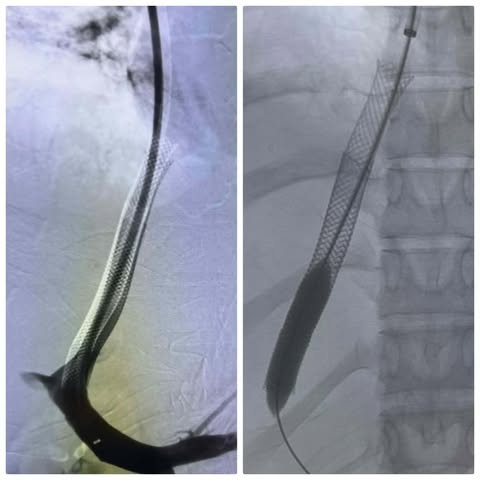

قام الفريق الطبي بإجراء عملية دقيقة لتركيب دعامات معدنية بين الوريد الأجوف السفلي والوريد البابي الكبدي باستخدام تقنية الـ (TIPSS)، والتي تُعد خياراً علاجياً متقدماً ينفرد به مستشفى الراجحي كونه المركز الوحيد في صعيد مصر الذي يقدم هذه التقنية التي تتطلب مهارة ودقة فائقة وتجهيزات طبية خاصة.